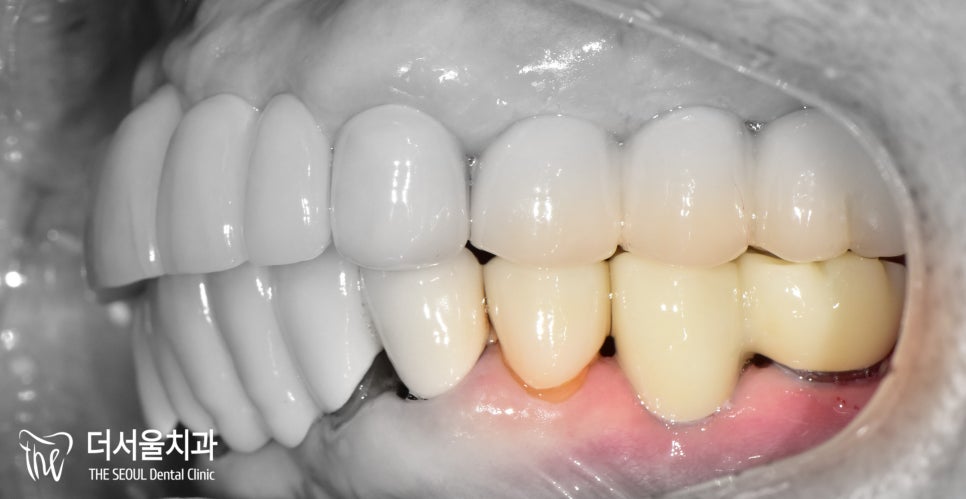

통증이 느껴졌던 오래된 브릿지가

튼튼하고 심미성이 좋은 지르코니아로

바뀌어 있는 모습을 확인할 수 있습니다.

교합도 잘 맞물리고 있었으며

크라운도 인접치 형태에 맞춰

조화롭게 제작이 되었습니다.